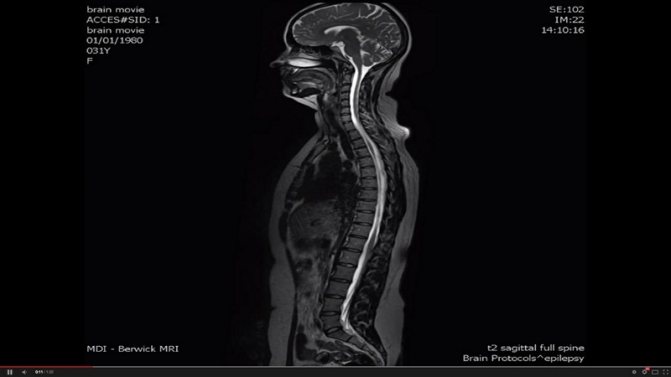

Магнитно-резонансной томографией (МРТ) является проведение достаточносложной, но неопасной и действенной методической процедуры с диагностической целью. При этом он никак не связан с применением ионизирующих излучений или какого-либо радиоактивного воздействия веществ. Применяются исключительно свойства магнитного поля совместно с импульсами радиочастот.

Этот метод позволяет исследовать пациента в тоннелеобразном отсеке томографа. На сегодняшний день считается наиболее эффективным диагностическим способом при выявлении прогрессирующих хронических отклонений от нормы в позвоночнике и грыж межпозвонковых дисков в частных случаях.

Преимущество такого обследования заключается в проведении наиболее тонкого детального изучения, как мягкой ткани, так и дискового строения, в том числе наличия разрыва его кольцеобразной структуры, нервных оснований, вещества спинного мозга. Визуальное восприятие врачами пораженных участков в наиболее полной мере исключает неясности при излечении многих проблем в позвоночнике.